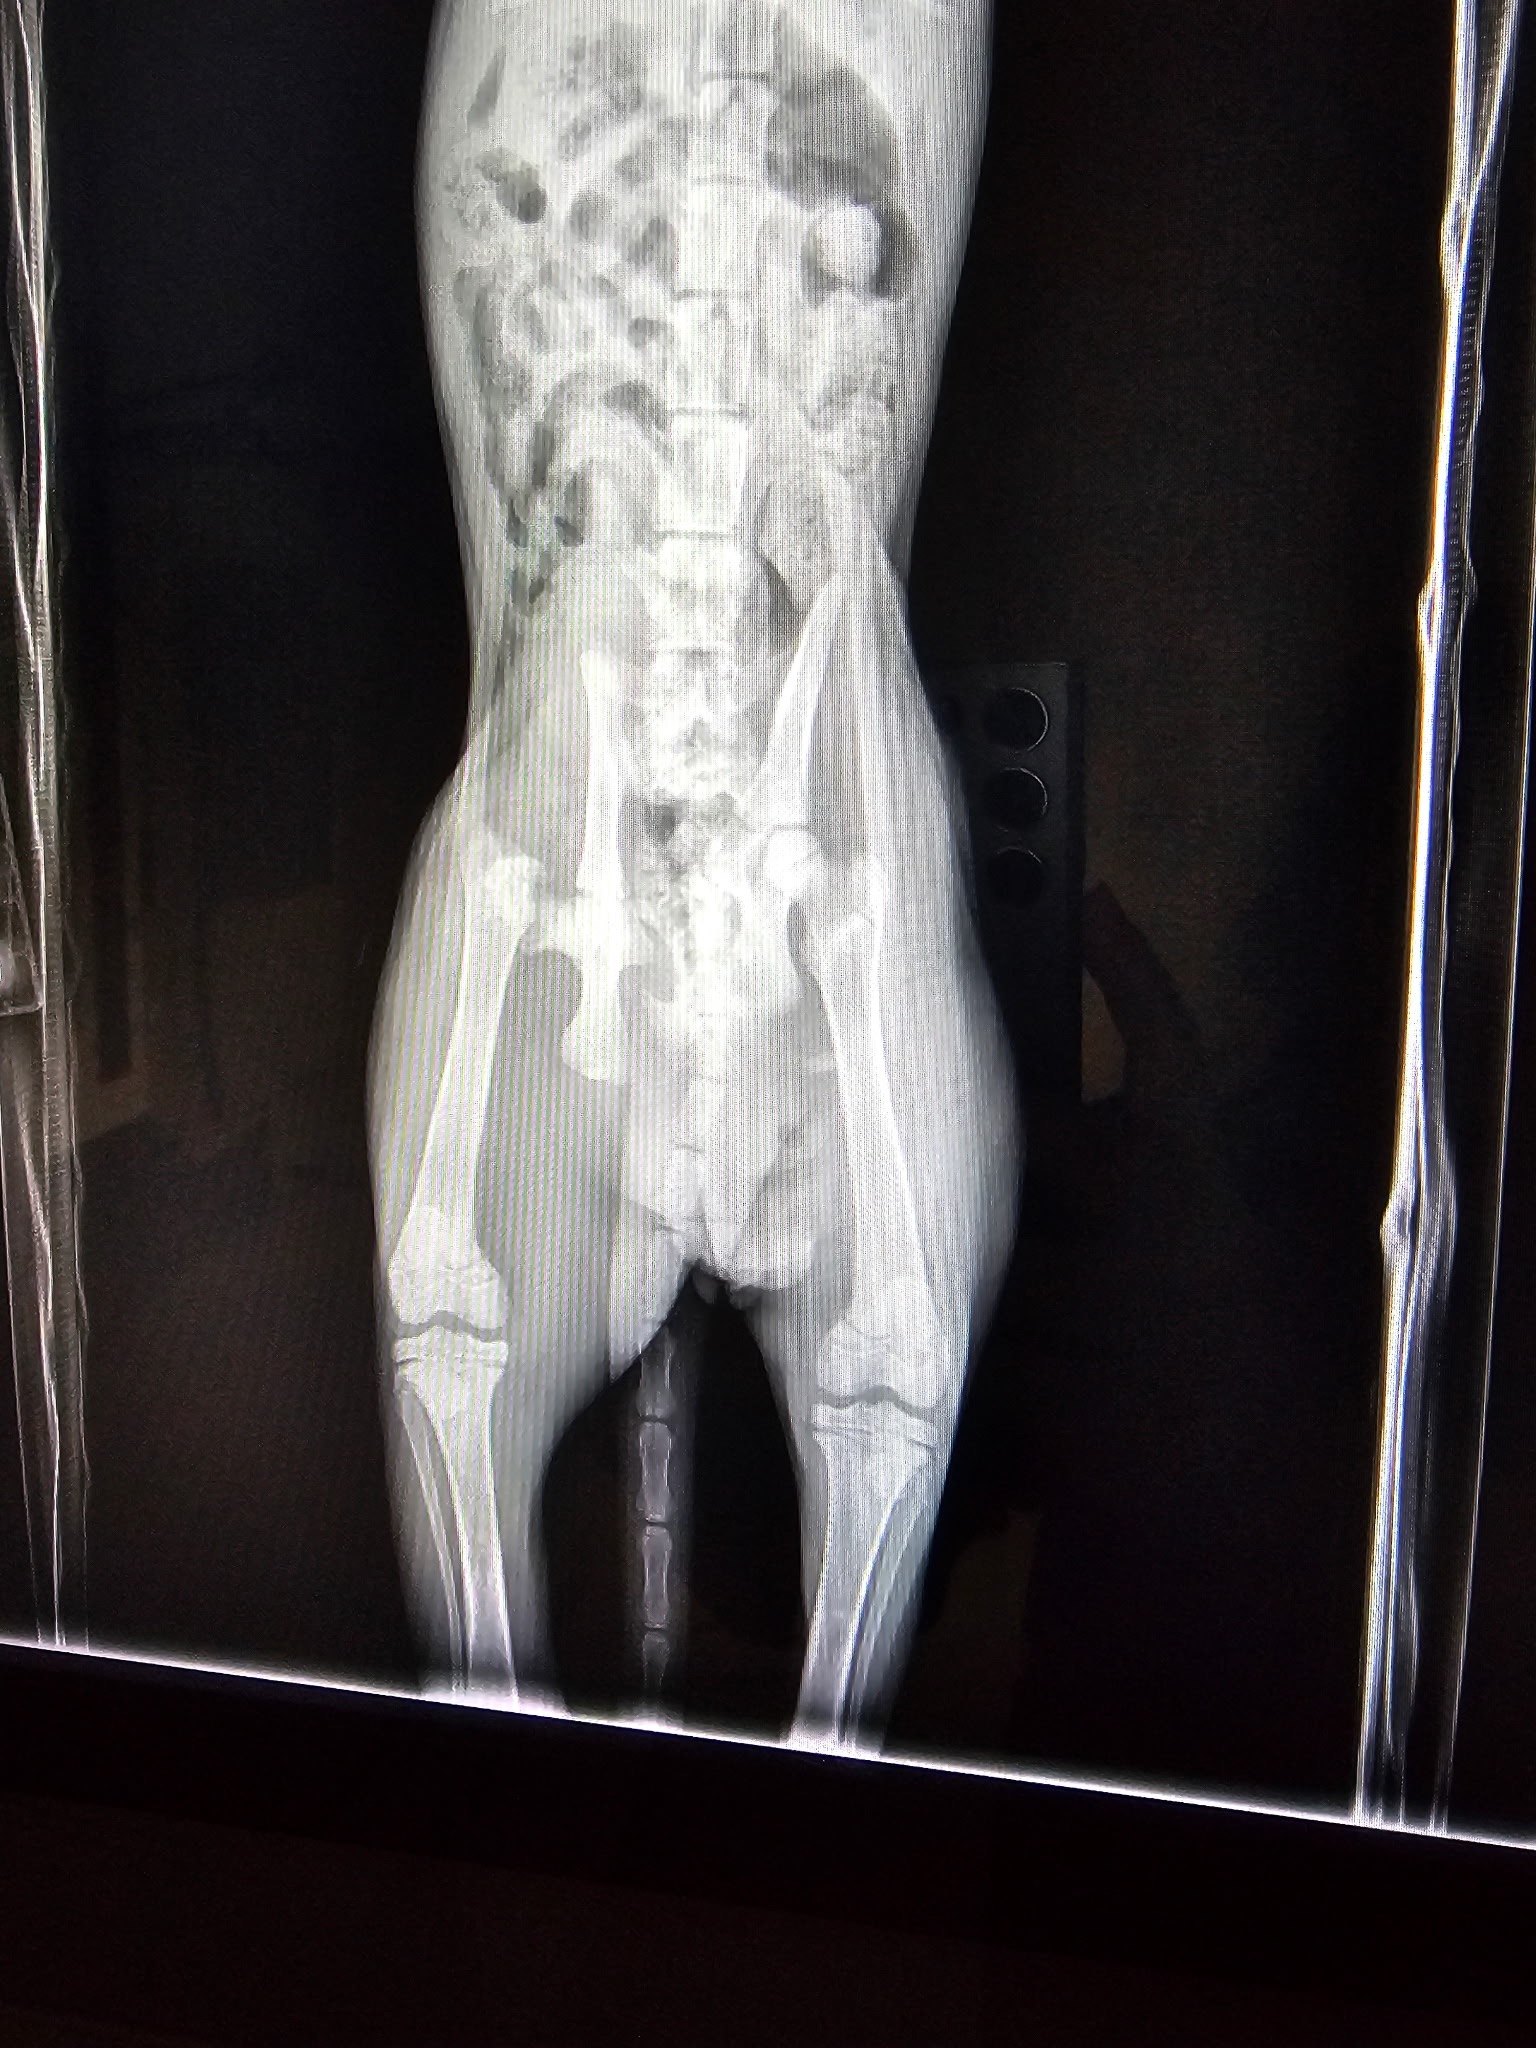

PLEASE KEEP SHARING any little bit helps. This baby cannot stay with a broken pelvis long. Please help save him!!! This baby only 3 months old was found by a sweet lady, that found him laying on the street. I met her at the vet and she was on her way to take him to be euthanized at Seacca, as the cost of surgery was too much. I spoke with the doctor and he said he can be saved with surgery. His pelvis is broke so it’s urgent to get it done asap. I am praying we can save this sweet boy!!! Please share for donations. It will be around 4k, I will have a complete bill soon. Thank you and bless you all!!!